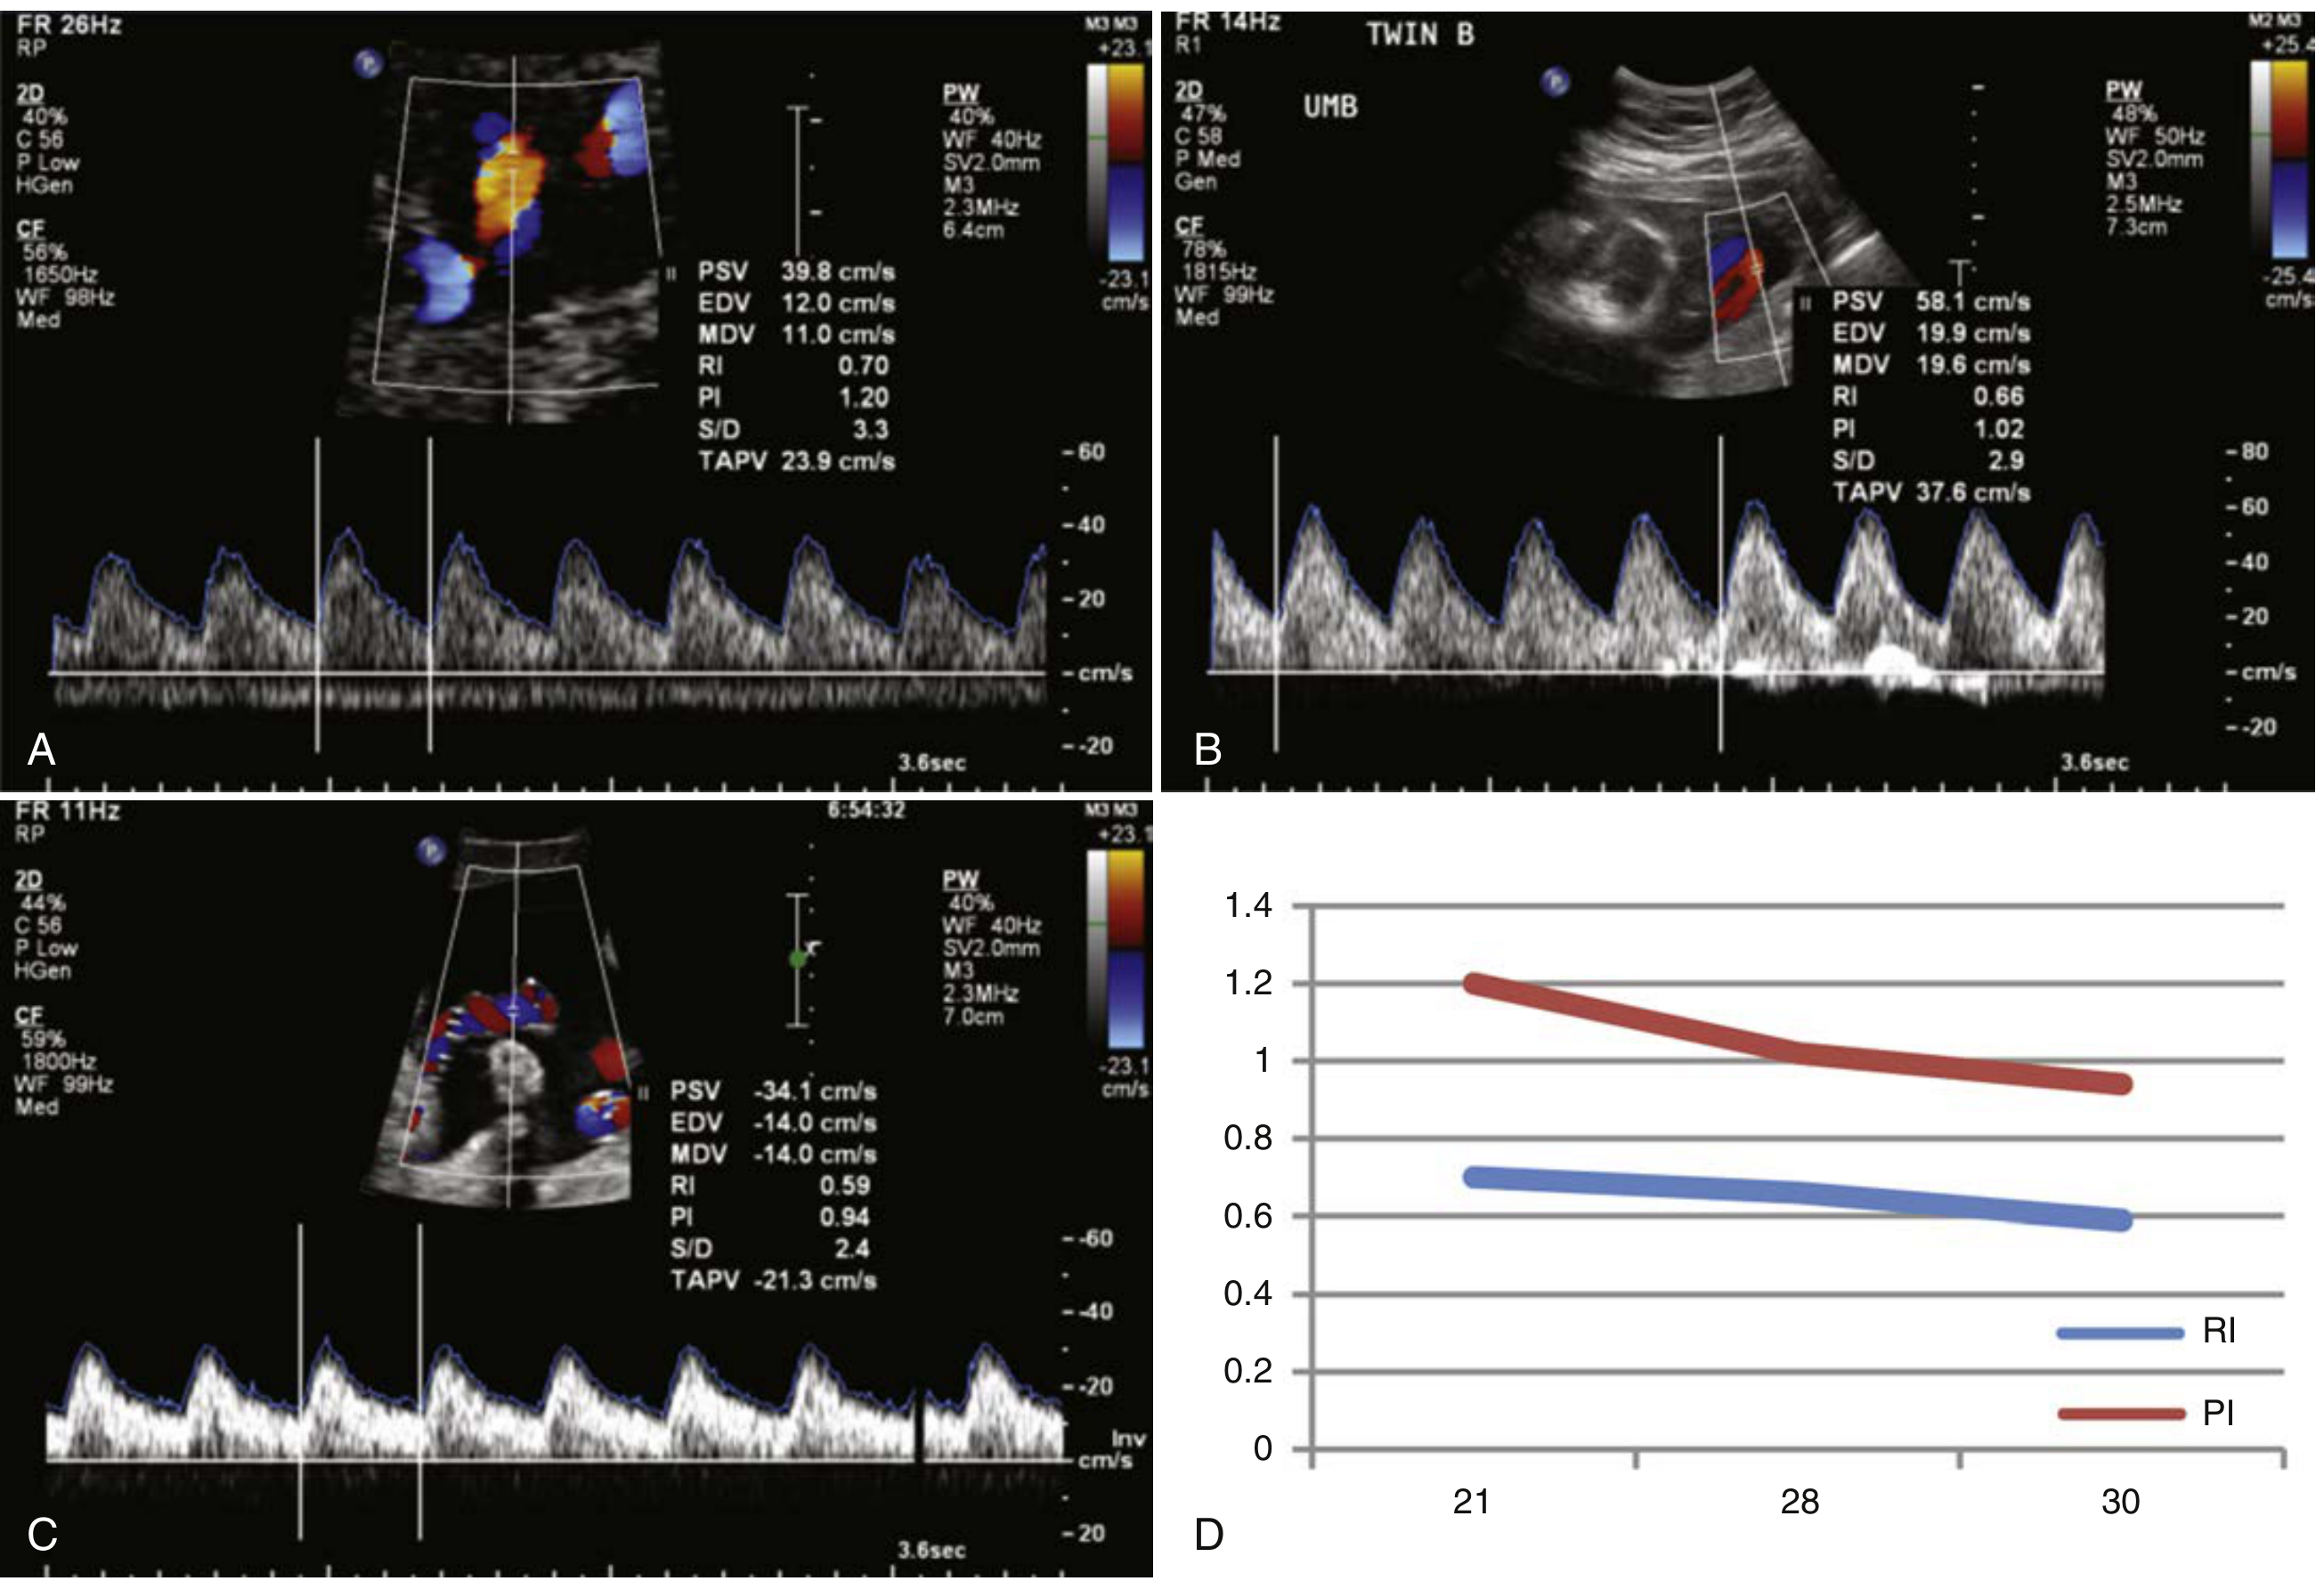

From the textbook image (Creasy & Resnik): at 21 weeks PI ≈ 1.20, declining to ≈ 0.94 by 30 weeks.

Umbilical artery RI and PI values from 21–30 weeks showing progressive decline

Umbilical artery RI and PI values 21–30 weeks (panel D). RI (blue) ~0.70→0.59; PI (red) ~1.20→0.94 — Creasy & Resnik's Maternal-Fetal Medicine